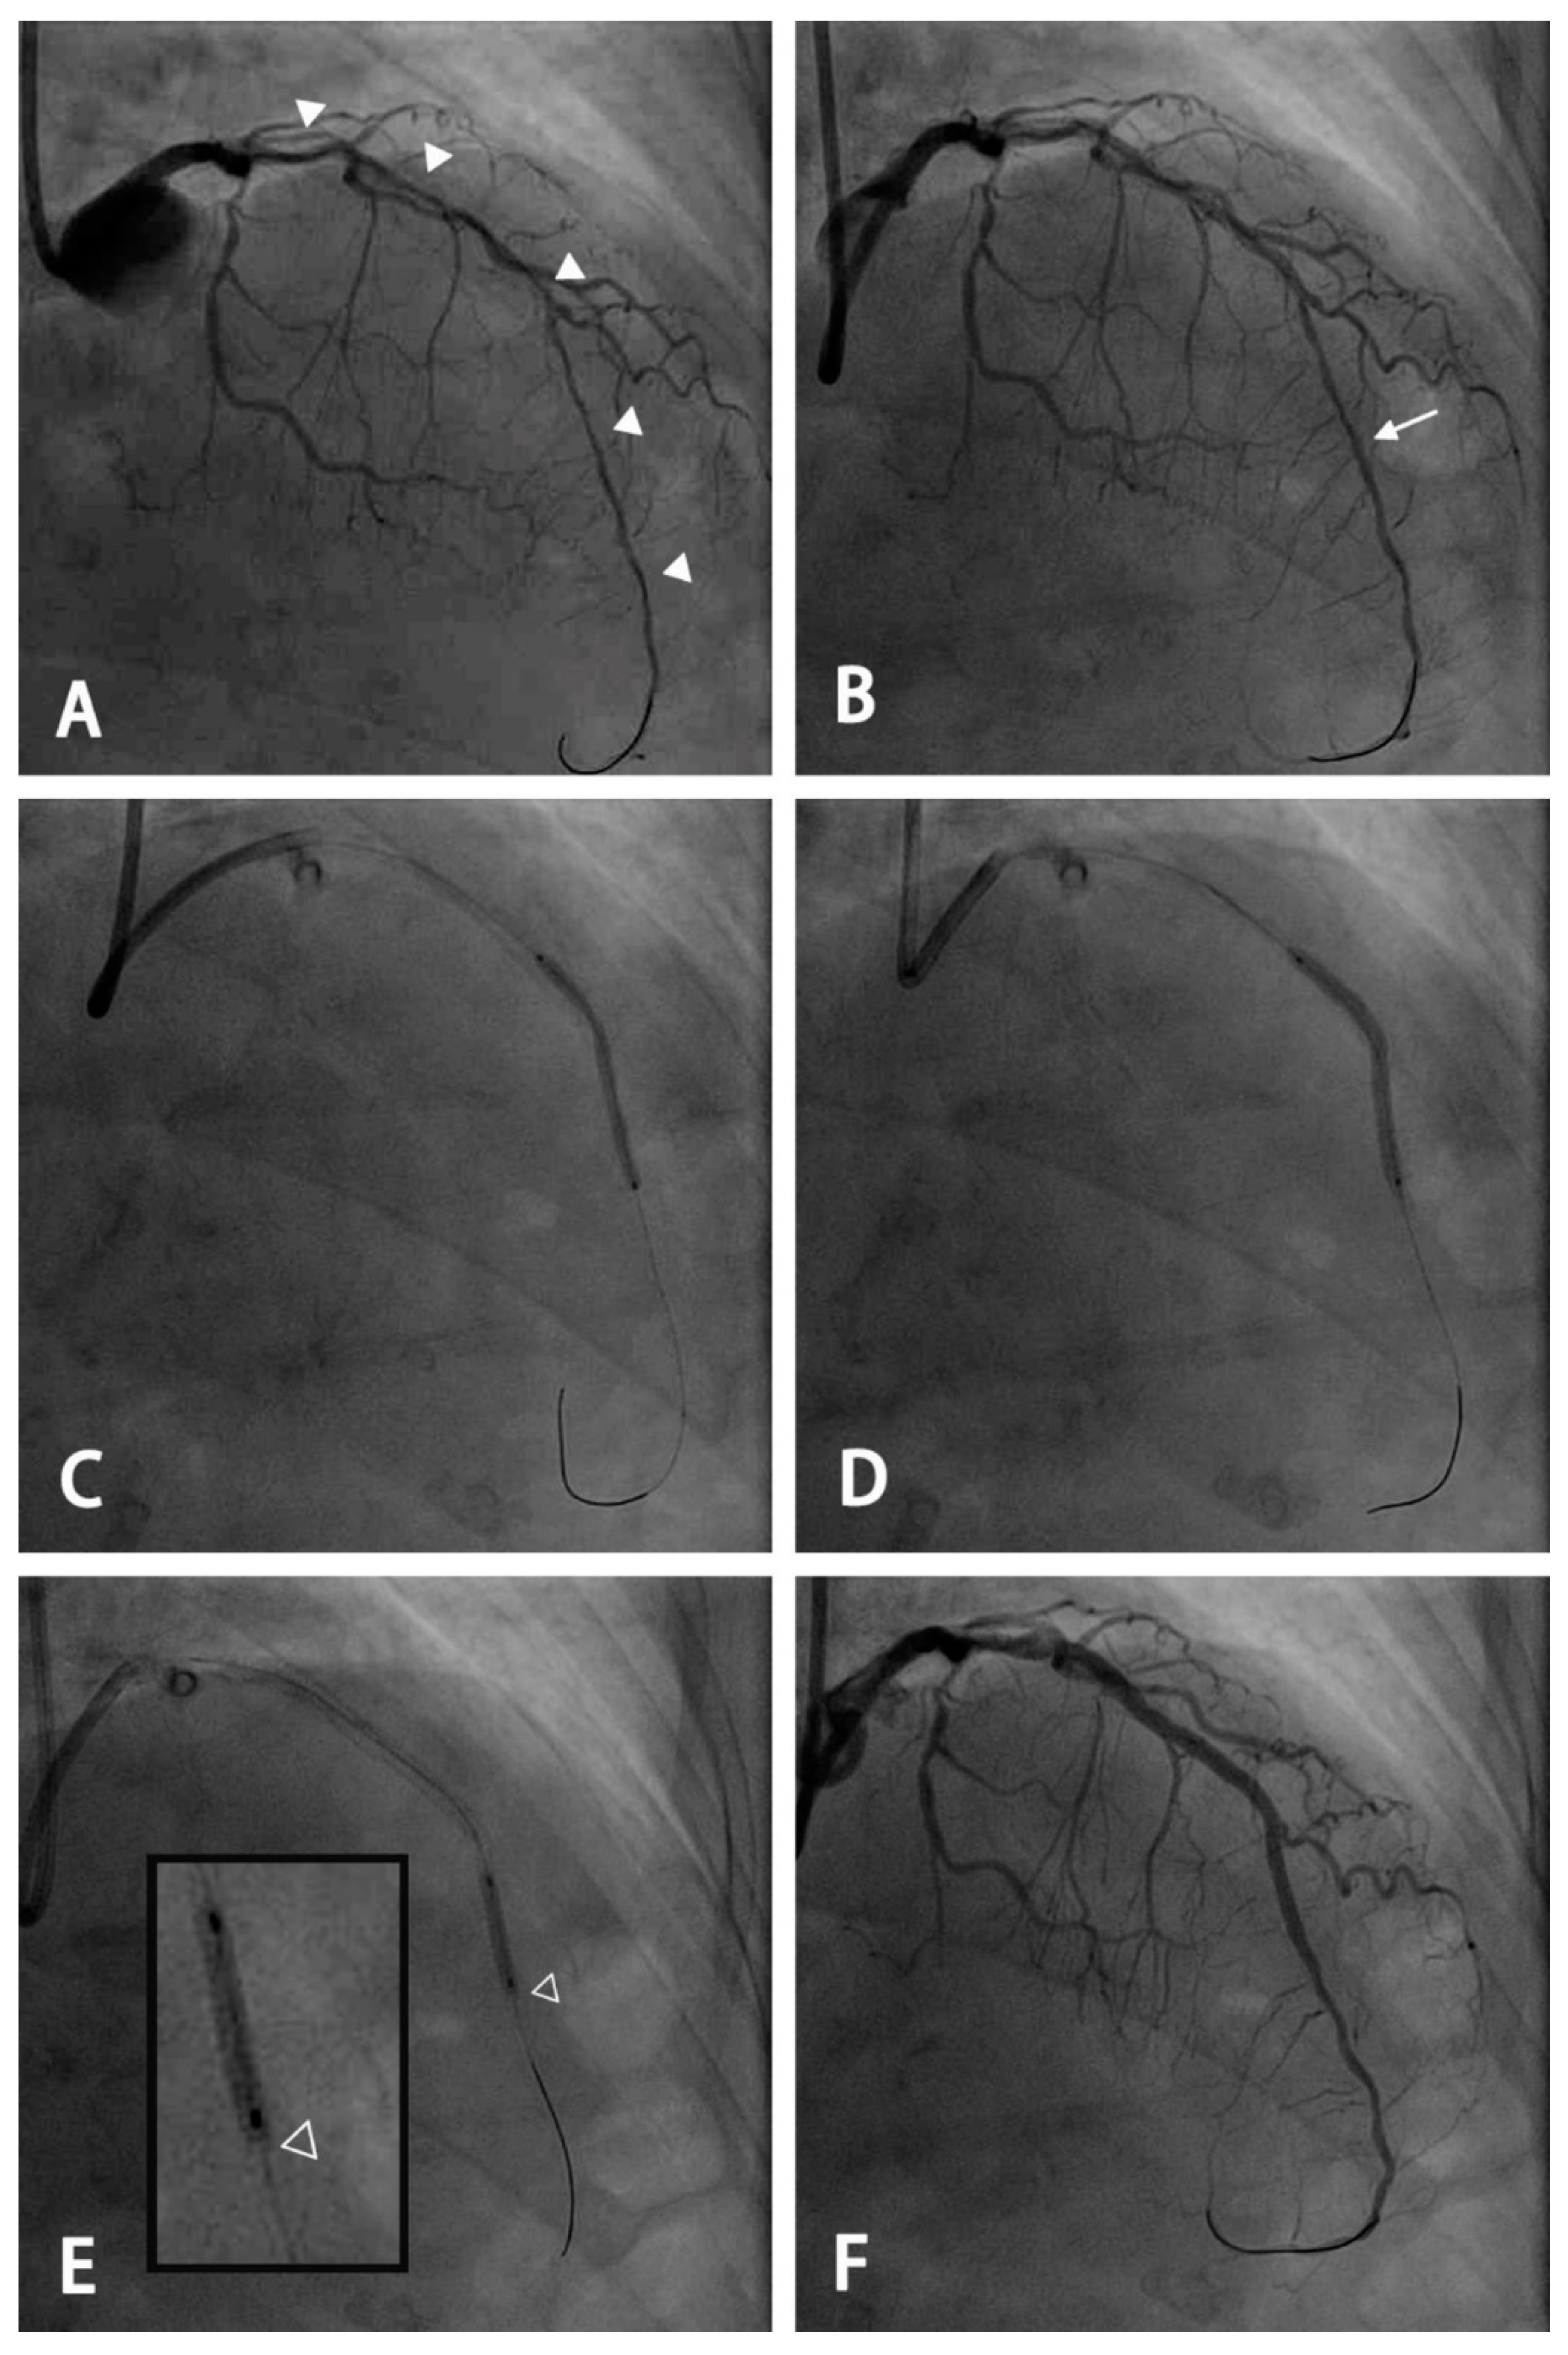

2.2. PCI Procedure